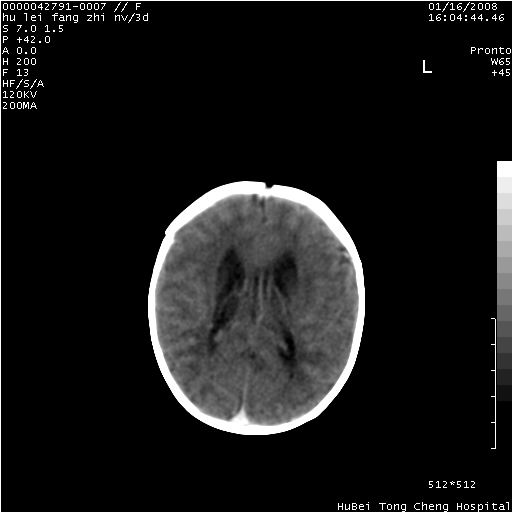

患儿 女,3天。惊跳,纳差。第二胎顺产,羊水ⅱ度。

临床诊断:hie?

颅脑ct轴位平扫(层厚、层距均为7mm),图像如下:

hie合并蛛网膜下腔出血

hie合并蛛网膜下腔出血,五、六脑室形成。

支持hie伴少量蛛血.

支持胼胝体发育不良。

支持hie,胼胝体发育差些

支持胼胝体发育不良